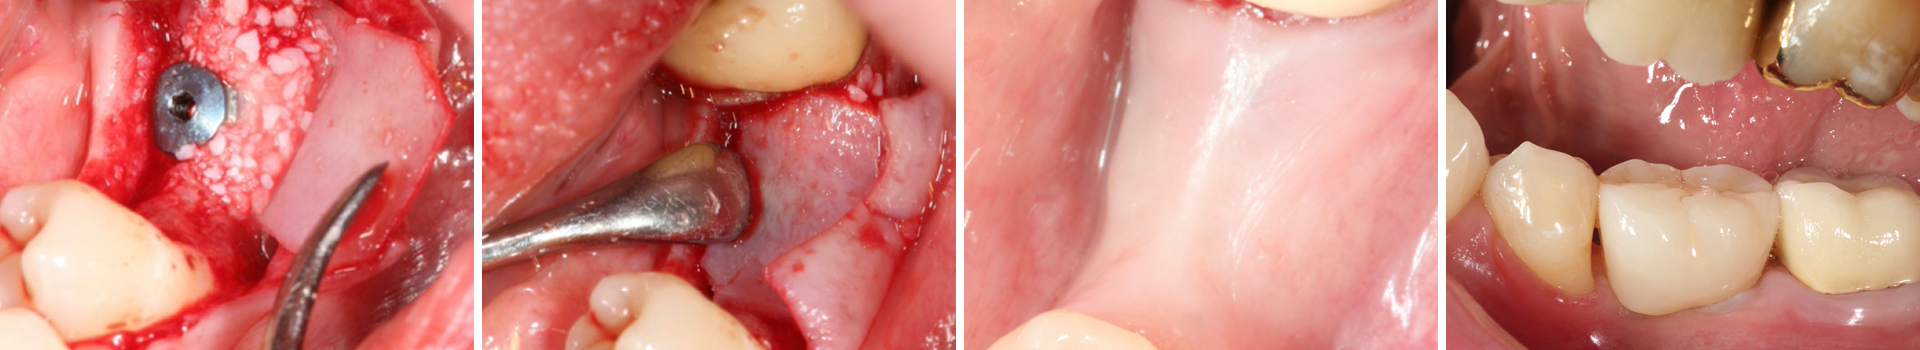

Simultane Implantation und Augmentation Regio 36

Nach Implantation wurde die zugeschnittene Bone Lamina positioniert und mit Pins fixiert, die Situation danach ist in Abb. 5 zu sehen. Mit dem Instrument wird demonstriert, dass eine „Tasche“ geschaffen wurde, die in Abb. 6 mit mp3® Knochengranulat aufgefüllt wird. Abb. 7 stellt dar, wie die Bone Lamina über den Kopf des Implantates auf den lingualen Anteil des Kieferkammes positioniert wird.

Nach Implantation: Positionierung und Fixierung der Bone Lamina.

Abbildung 5